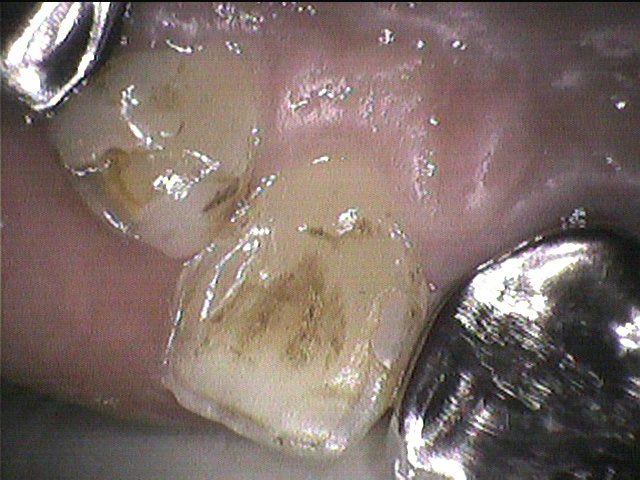

◎クリーニング前のお写真